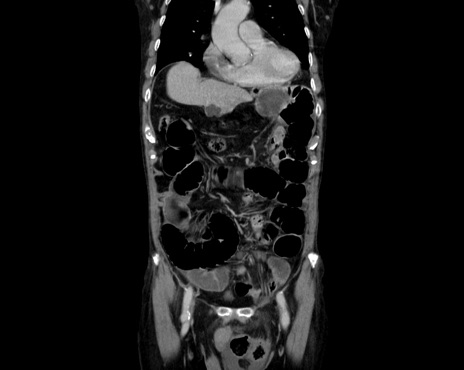

症例26(冠状断像)

【症例】80歳代男性

【主訴】嘔吐

【現病歴】昨晩2回嘔吐あり、今朝になっても嘔吐あり。来院。

【既往歴】胃潰瘍

【身体所見】意識清明、BT 37.6℃、BP 166/95mmHg、HR 100bpm、SpO2 97%、腹部:平坦・軟、腸蠕動音聴取良好、圧痛なし。

【データ】WBC 21900、CRP 1.4

横断像